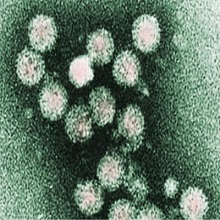

Вирус хепатитиса Ц (ХЦВ) припада РНК вирусима, фамилија „Flaviviridae". Геном чини једнострука РНК а омотач протеини, величине је 35-50 нм. Показује хиперваријабилност регија генома и до сада је описано 12 генотипова. |